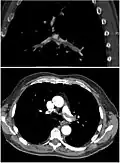

CT pulmonary angiography

CT pulmonary angiography (CTPA) is a pulmonary angiogram obtained using computed tomography (CT) with radiocontrast rather than right heart catheterization. Its advantages are that it is accurate, it is non-invasive, it is more often available, and it may identify other lung disorders in case there is no pulmonary embolism. The accuracy and non-invasive nature of CTPA also make it advantageous for people who are pregnant.[61]

On CT scan, pulmonary emboli can be classified according to the level along the arterial tree. -

Segmental and subsegmental pulmonary emboli on both sides -

CT pulmonary angiography showing a "saddle embolus" at the bifurcation of the main pulmonary artery and thrombus burden in the lobar arteries on both sides

Assessing the accuracy of CT pulmonary angiography is hindered by the rapid changes in the number of rows of detectors available in multidetector CT (MDCT) machines.[62] According to a cohort study, single-slice spiral CT may help diagnose detection among people with suspected pulmonary embolism.[63] In this study, the sensitivity was 69% and specificity was 84%. In this study which had a prevalence of detection was 32%, the positive predictive value of 67.0% and negative predictive value of 85.2%. However, this study's results may be biased due to possible incorporation bias, since the CT scan was the final diagnostic tool in people with pulmonary embolism. The authors noted that a negative single-slice CT scan is insufficient to rule out pulmonary embolism on its own. A separate study with a mixture of 4-slice and 16-slice scanners reported a sensitivity of 83% and a specificity of 96%, which means that it is a good test for ruling out a pulmonary embolism if it is not seen on imaging and that it is very good at confirming a pulmonary embolism is present if it is seen. This study noted that additional testing is necessary when the clinical probability is inconsistent with the imaging results.[64] CTPA is non-inferior to VQ scanning, and identifies more emboli (without necessarily improving the outcome) compared to VQ scanning.[65]